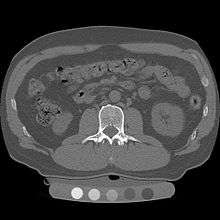

Quantitative computed tomography (QCT) is a medical technique that measures bone mineral density (BMD) using a standard X-ray Computed Tomography (CT) scanner with a calibration standard to convert Hounsfield Units (HU) of the CT image to bone mineral density values.[1] Quantitative CT scans are primarily used to evaluate bone mineral density at the lumbar spine and hip.

In general, solid phantoms placed in a pad under the patient during CT image acquisition are used for calibration. These phantoms contain materials that represent a number of different equivalent bone mineral densities. Usually either calcium hydroxyapatite (CaHAP) or potassium phosphate (K2HPO4) are used as the reference standard.[2]

Originally, conventional 2D QCT used individual, thick CT slice images through each of multiple vertebrae which involved tilting the CT scanner gantry to align the slice with each vertebra. Today, modern 3D QCT uses the ability of CT scanners to rapidly acquire multiple slices to construct three-dimensional images of the human body. Using 3D imaging substantially reduced image acquisition time, improved reproducibility and enabled QCT bone density analysis of the hip.[1]

QCT scan protocols are low-dose and can limit the amount of radiation exposure to between 200-400µSv for a spine exam[6] This is comparable to a set of mammograms and typically substantially less than a standard CT exam. Using other non-IV contrast abdominal or pelvic scans such as a Virtual Colonography studies, the QCT exam can be performed without requiring any further image acquisition or consequent radiation dose to the patient.[7]

Dual use of CT images

Several studies have shown that bone density may be measured by QCT using CT images that were ordered for other purposes. Using pre-existing images, including CT colonography exams,[14] QCT allows for bone density screening without submitting the patient to any additional radiation exposure. The feasibility of using routine abdominal contrast-enhanced CT scans for the evaluation of bone density by QCT has also been demonstrated.[15]